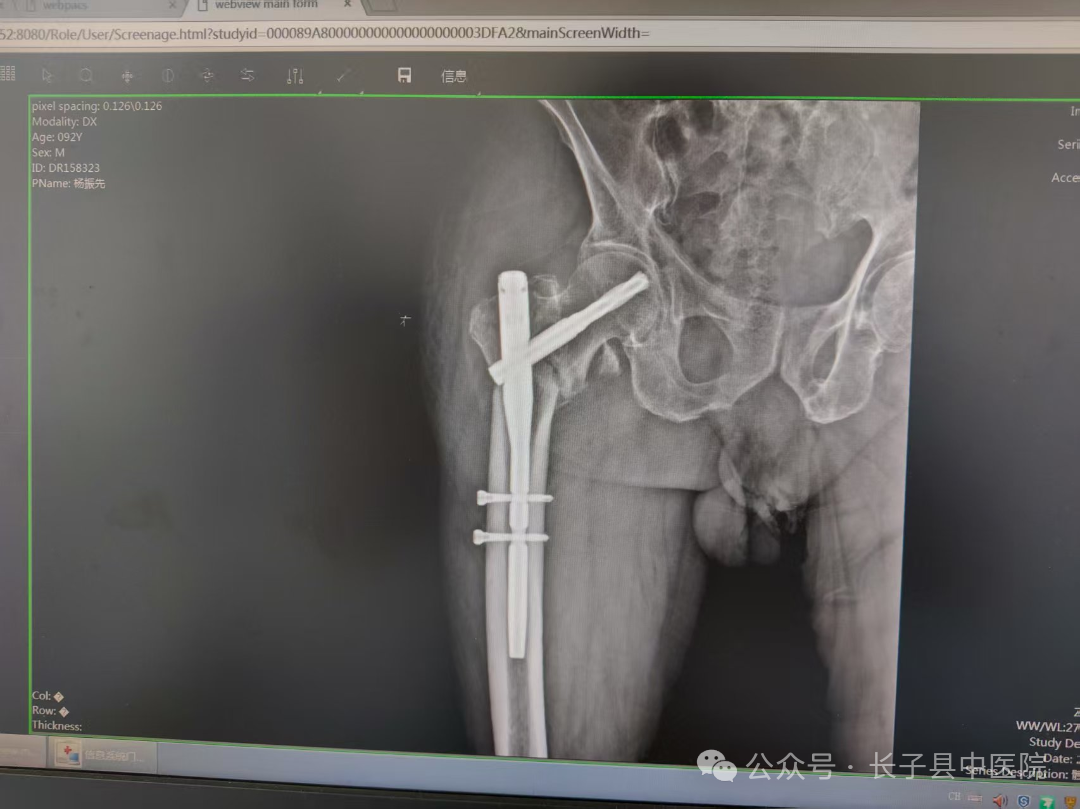

面对如此复杂的情况,我院骨伤科主任李志强及主管大夫李伟与医护团队(骨科全体、内科、手术麻醉科、彩超室、医务科)进行了周密的术前讨论,共同探讨最佳的手术方案,经过反复权衡,最终确定了手术策略,完善相关检查后,排除手术禁忌证,行右股骨粗隆间骨折闭合复位PFNA内固定术,手术时间仅用了1小时,术中、术后输血共800ml,以补充血容量,纠正贫血,手术过程严格无菌操作,在骨折复位时,确保对位对线良好。整个手术过程顺利。

术后三天,杨大爷伤口无明显红肿渗出,刀口呈甲级愈合。术后一周,杨大爷康复出院,责任医生与护士为杨大爷及家属详细讲解了出院后的康复训练方法及复诊时间,他们的脸上露出了久违的笑容,“感谢医生们用精湛的技术解除了我的痛苦,也感谢你们一直陪伴着我,给予我信心与鼓励!”